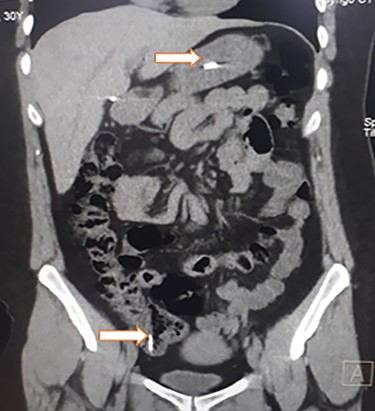

Abdominal CT, revealing two metal bodies, one in the stomach and one in the cecum.

On clinical examination, a dehydrated and tachycardic (112 bpm) patient was encountered, she had diffuse pain in her lower abdomen without tenderness. After reanimation, an abdominal X-ray found two metal bodies in the bowel (Fig. 1); therefore, a computed tomography (CT) was requested, which revealed two metal foreign bodies, (razor blades) one in the stomach and one in the cecum without pneumoperitoneum (Fig. 2). As the patient did not have any tenderness, an upper endoscopy and colonoscopy were planned. During the upper endoscopy, the razor blade was detected in the antrum and was embedded in the mucosa (Fig. 3). After several failed attempts to remove the foreign object, the procedure was interrupted due to a risk of inadvertent perforation, and surgery was decided.